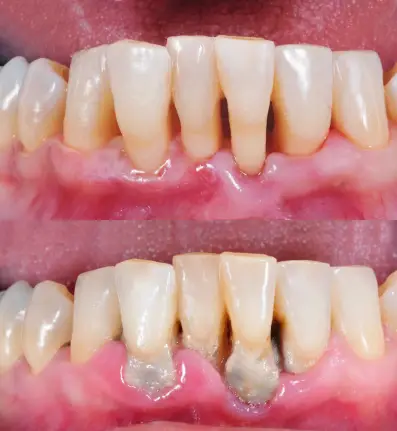

잇몸에 갇힌 박테리아와 음식 부스러기가 축적되어 구취가 남을 수 있습니다. 건강한 잇몸은 분홍색이며 단단해야 합니다. 잇몸이 붉어지거나 부어 오르면, 이는 플라크 축적으로 인한 감염의 징후일 수 있습니다.

이와 같은 증상이 나타날 경우, 치과 의사를 방문하여 적절한 치료를 받는 것이 중요합니다. 잇몸 건강은 전체적인 건강에 큰 영향을 미치므로 꾸준한 관리가 필수적입니다.잇몸병은 흔하고 중요한 구강 질환입니다. 잇몸의 혈관이 염증을 일으키면, 잇몸이 붉게 발적하거나 출혈할 수 있습니다. 치은염은 잇몸병 중 가장 흔한 것으로, 초기 단계에서 치아 주변을 둘러싸고 있는 섬유로 덮인 조직의 염증을 나타냅니다. 피가 나지 않는 건강한 잇몸은 무엇보다도 중요합니다. 정기적인 칫솔질과 구강 세안은 잇몸병을 예방하고 조기 발견할 수 있습니다.

- 잇몸병은 잇몸이 붉거나 출혈하는 상황을 두고 일반적으로 사용됩니다.

- 치은염은 잇몸병 중 가장 흔한 형태로서, 잇몸 주변 조직의 염증을 나타냅니다.

- 건강한 잇몸에서는 피가 나지 않아야 하며, 치은염의 초기 징후 중 하나로 지속적인 출혈이 있습니다.